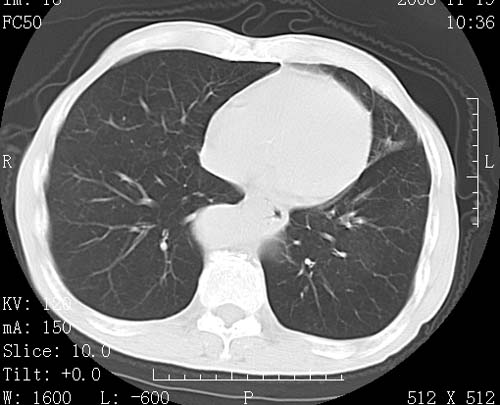

术前查体,双肺部结节是转移?结核?请点评

转移 隆突下淋巴结亦肿大

首先考虑转移,纵隔内淋巴结亦肿大;

1)符合食管癌表现。2)两肺及纵隔淋巴结多发性转移瘤。3)左肺上叶舌段及两肺下叶炎症感染。

食管癌伴双肺转移,评述:肺部毛细血管网丰富,全身血液均快速流经肺部,癌细胞容易过滤定植,形成转移瘤,影象特点为以毛细血管末梢为中心的结节灶,边缘光滑锐利,少见有中心空洞着,不同来源的转移瘤可有各自特点,如甲状腺癌为双肺弥漫性微结节,本例有原发灶,双肺影象灶典型,左肺舌段条带状网格样伴胸膜天幕征,可视为癌性淋巴管炎。